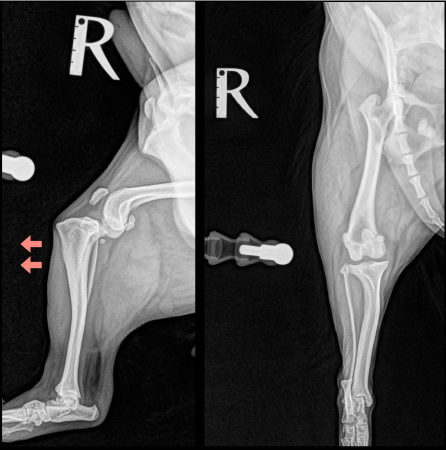

<術前のレントゲン>

前十字靭帯断裂により、脛骨が前方変位しています。